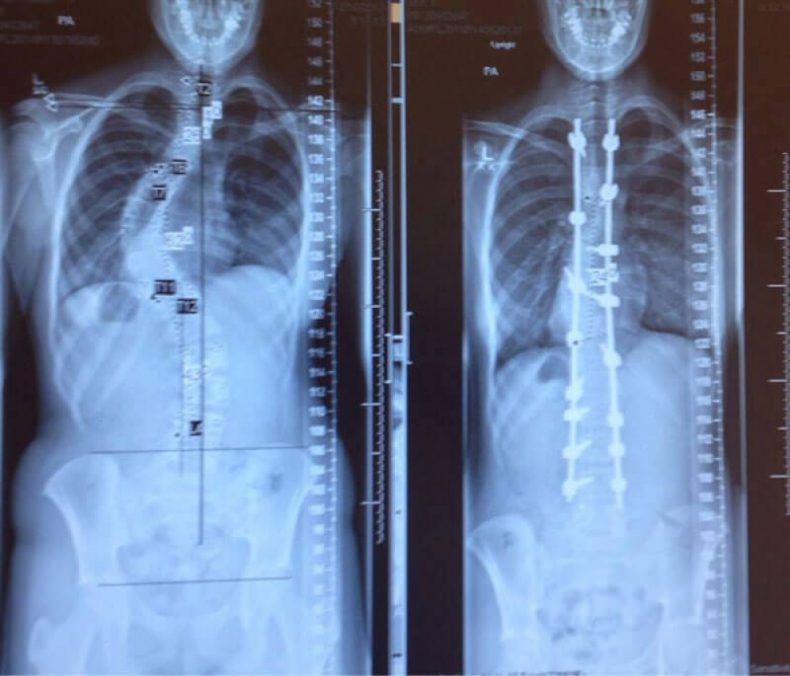

- Ce patient a été traité pour la scoliose, voici le rayon X de sa colonne vertébrale, avant et après le traitement.